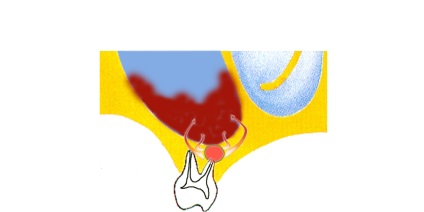

A „odontogén ciszta sinus” kifejezés az orvosok ciszta (kóros buborék / üreg megtöltve,) eredményeként képződött a Tooth betegség.

Diagnosztizálása odontogén ciszták (és más odontogén sinus léziók), két összetevője van. Először is, meg kell határozni, hogy pontosan milyen fogat volt az oka, és az állam volt az, másrészt, hogy meghatározza a helyzetét a melléküregek, beleértve a ciszta mérete és elhelyezkedése is.